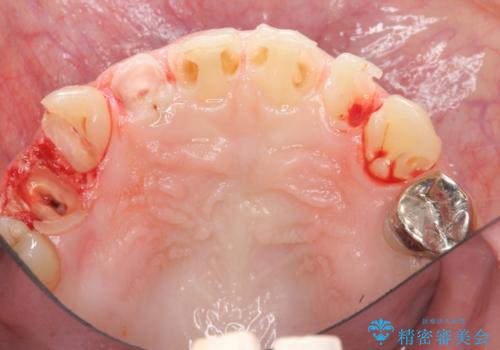

- 放置した虫歯の歯がボロボロになってしまい治療を希望され来院されました。

残根状態の歯、神経まで虫歯が達し失活した歯、歯肉縁下まで及んだ虫歯が多数認められます。

まず虫歯を拡大鏡、マイクロスコープ下で丁寧に取り除き歯肉縁下の虫歯を歯周外科により解決したのち、ジルコニアクラウン製作を行っていきます。